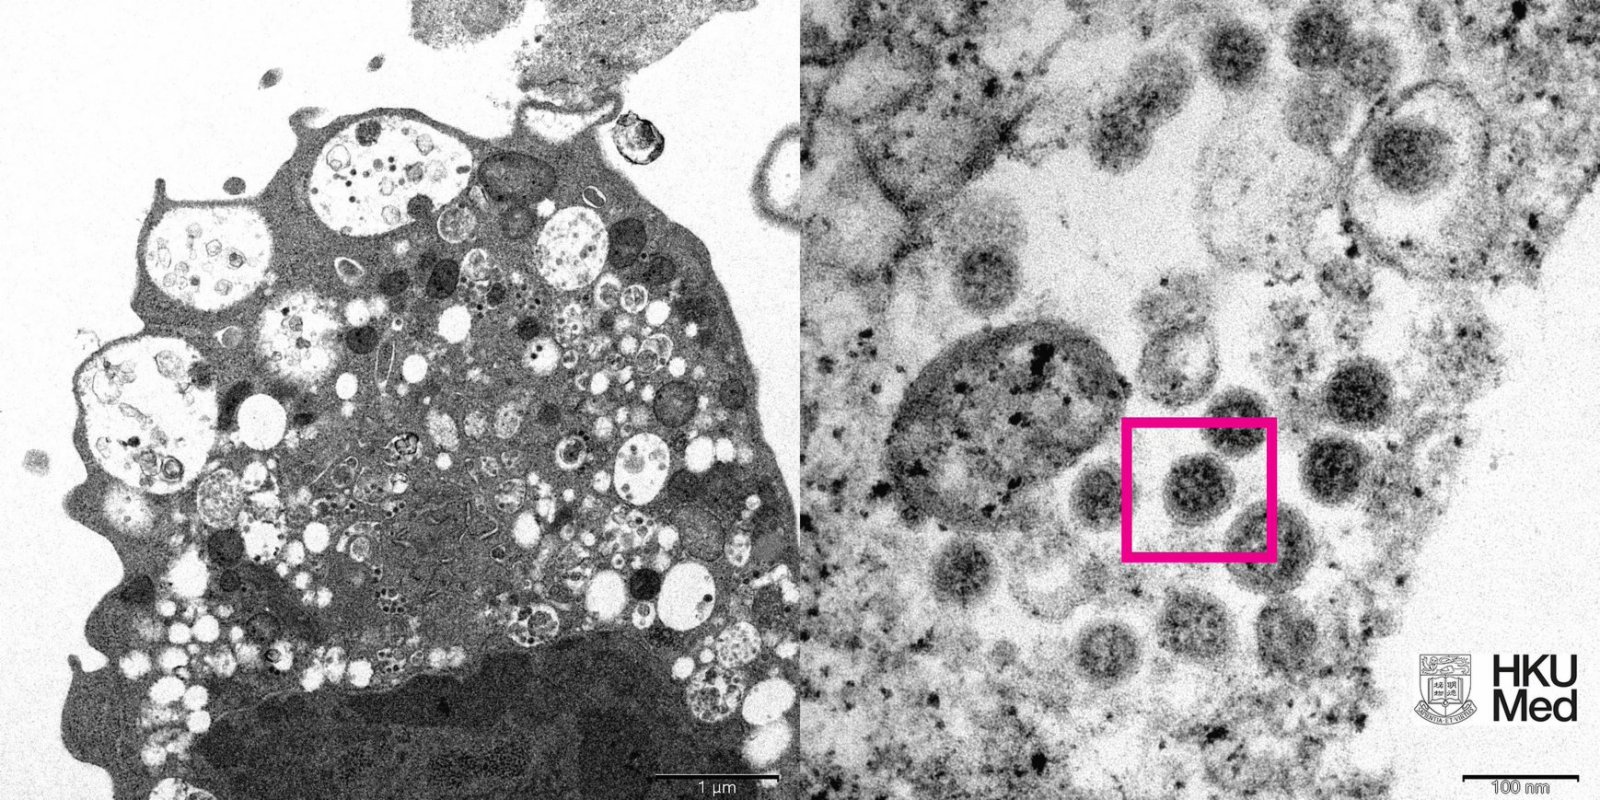

新型變種病毒株Omicron肆虐全球,繼早前成功分離及培養病毒株Omicron後,港大醫學院袁國勇團隊今日(8日)再公布電子顯微鏡下新冠病毒Omicron變異株的照片。

根據港大醫學院發布的圖片顯示,在低倍電子顯微鏡下,感染Omicron新型變異病毒株後的猴腎細胞(Vero E6)受損,腫脹囊泡,囊泡內含有黑色小病毒顆粒;而在高倍電子顯微鏡下,受感染的Vero E6細胞,病毒顆粒表面呈現皇冠形的刺突蛋白。

圖左:低倍電子顯微鏡下感染新型冠狀病毒Omicron變異株後的猴腎細胞(Vero E6)受損,腫脹囊泡,囊泡內含有黑色小病毒顆粒。圖右:高倍電子顯微鏡下受感染的Vero E6細胞,其表面呈現皇冠形的刺突蛋白(見紅框)。來源:香港大學醫學院